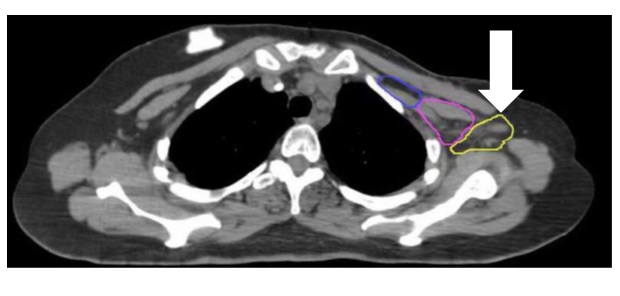

Na poniższym skanie TK strzałką oznaczono: